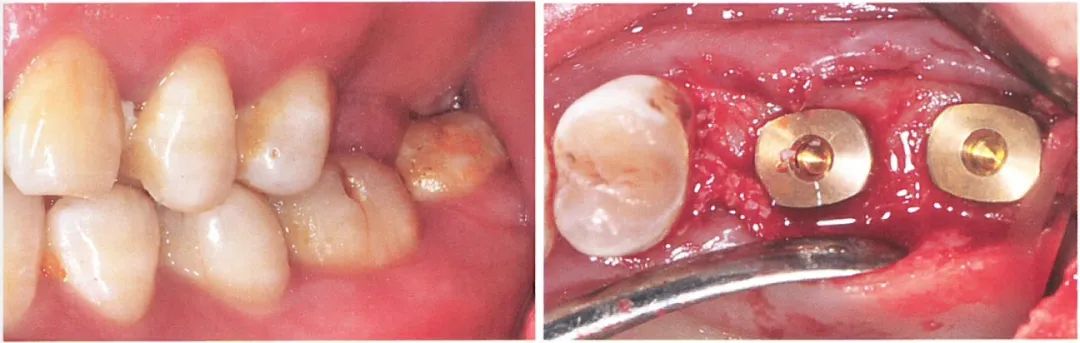

患者的26、27缺失,术前口内检查发现37明显伸长致使修复距离不足。如果只依靠调磨37的方式获得修复空间,调磨量会很大,极可能损伤牙髓。

与患者沟通后,患者选择正畸方式压低对颌牙。我们在26、27 位点植入两颗植体后,患者开始接受隐形矫治配合橡皮圈同时压低36、37。通过正畸压低的方式,患者的36、37与术前相比被明显压低。

术后6个月行二期手术更换愈合基台,使用6.5mm 高的愈合基台检测发现修复距离足够。